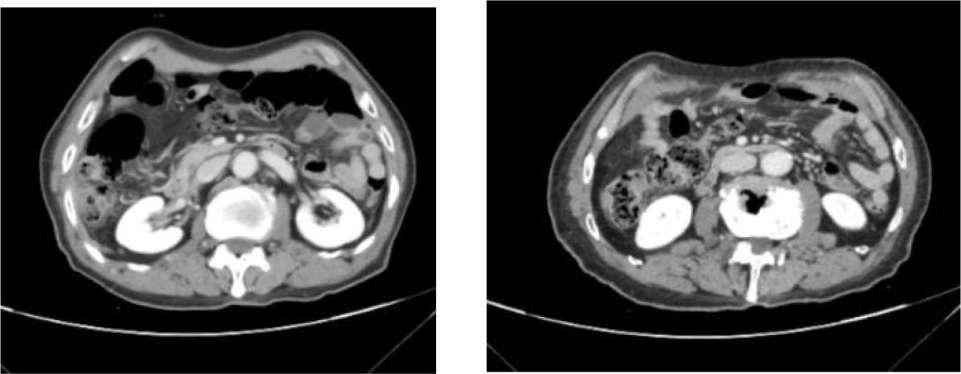

a) 胸部CT:诊断意见:左肺下叶占位,考虑肺Ca;结合临床。纵隔、左肺门淋巴结。胸壁软组织结节,考虑转移(图9)。

Figure 9. Results of chest CT examination

9. 胸部CT检查结果

b) 上腹部CT:诊断意见:肝脏多发囊肿。部分椎体变扁(未发现转移灶) (图10)。

Figure 10. Results of upper abdominal CT examination

10. 上腹部CT检查结果

影像学检查在多抗体阳性AE中常缺乏特异性。本例患者头颅MRI仅显示多发性脑梗死和脑白质脱髓鞘,未出现抗NMDAR脑炎常见的颞叶内侧高信号或抗GABABR脑炎的单侧/双侧颞叶异常[9]。这种“影像学阴性”表现约见于20%的多抗体阳性病例,可能与抗体对神经元功能的可逆性干扰而非结构性破坏有关[10]。胸部CT提示的左肺下叶占位及纵隔淋巴结肿大,结合神经元特异性烯醇化酶(94.24 ng/mL)和胃泌素释放前肽(>5000.00 pg/ml)的显著升高,高度提示SCLC的可能,而胸壁肿物病理检出的鳞状上皮细胞进一步支持恶性肿瘤的诊断[11]